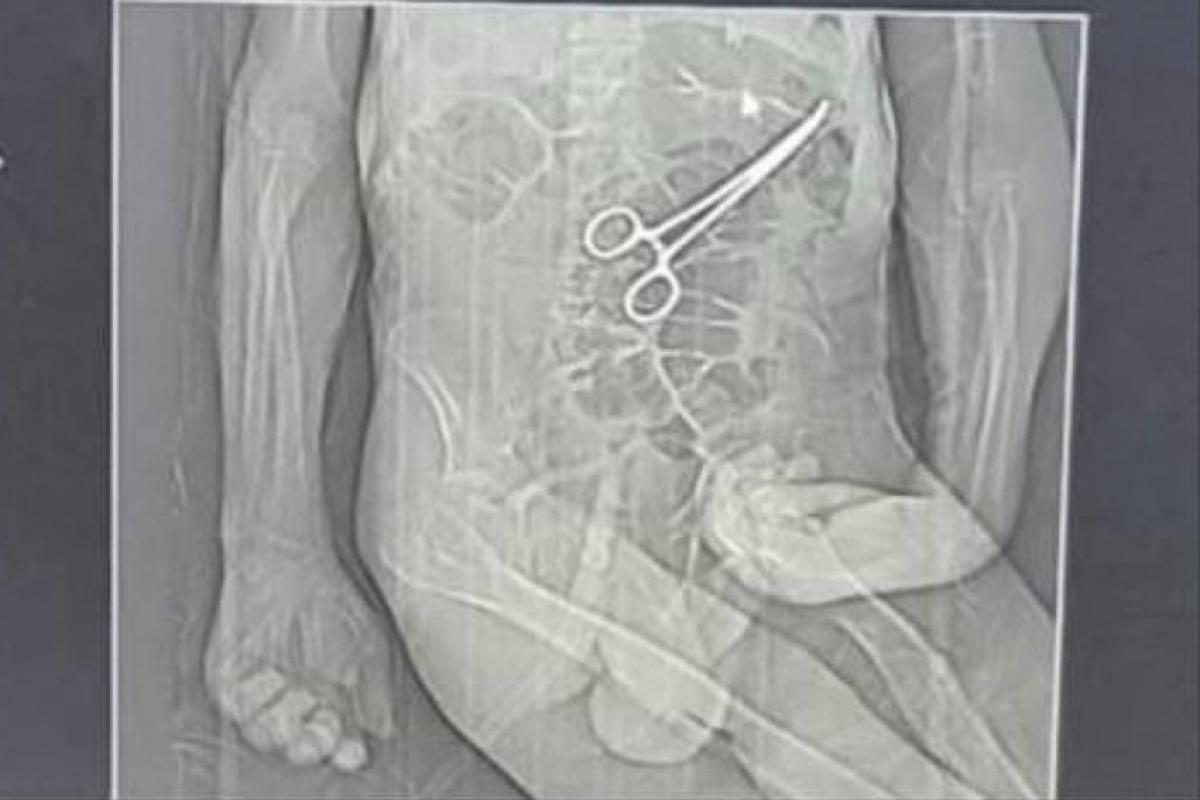

Tomografia usada pela família para acusar médicos de hospital de João Pinheiro (MG) de deixar pinça no abdômen do idoso após cirurgia

Após a cirurgia, o paciente voltou a apresentar sintomas graves, o que levou à realização de novos exames. Nesse momento, uma tomografia identificou, segundo a secretaria, "um corpo estranho na cavidade abdominal".

Os parentes também afirmam que só souberam do que de fato havia ocorrido por meio de uma reportagem de uma rádio local, quando tomaram conhecimento da imagem de uma tomografia indicando uma pinça no abdômen de Manoel.